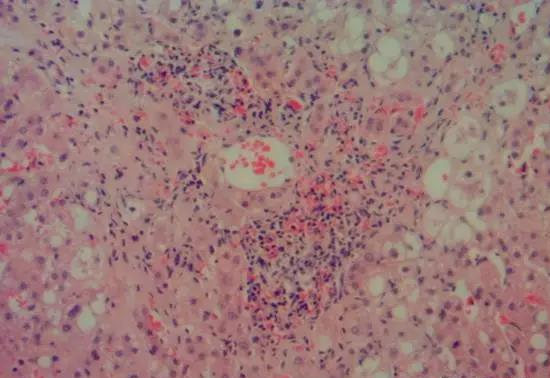

病理见肝脏以3区病变为主,脂肪细胞变性,大泡性为主,肝细胞水肿、气球样变,小叶炎较重,肝纤维化窦周纤维化明显,可见Mallory酒精小体。

最后诊断酒精性肝炎并发展成酒精性肝纤维化。